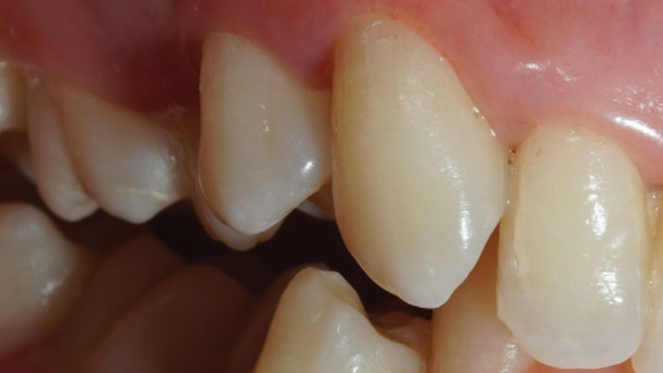

Хронический пародонтит средней степени тяжести

Результат через 2 недели

Вектор терапия по схеме, затем ФДТ 2-3 раза в неделю Сочетание периоскан, вектор-терапии и ФДТ 2-3 раза через неделю.